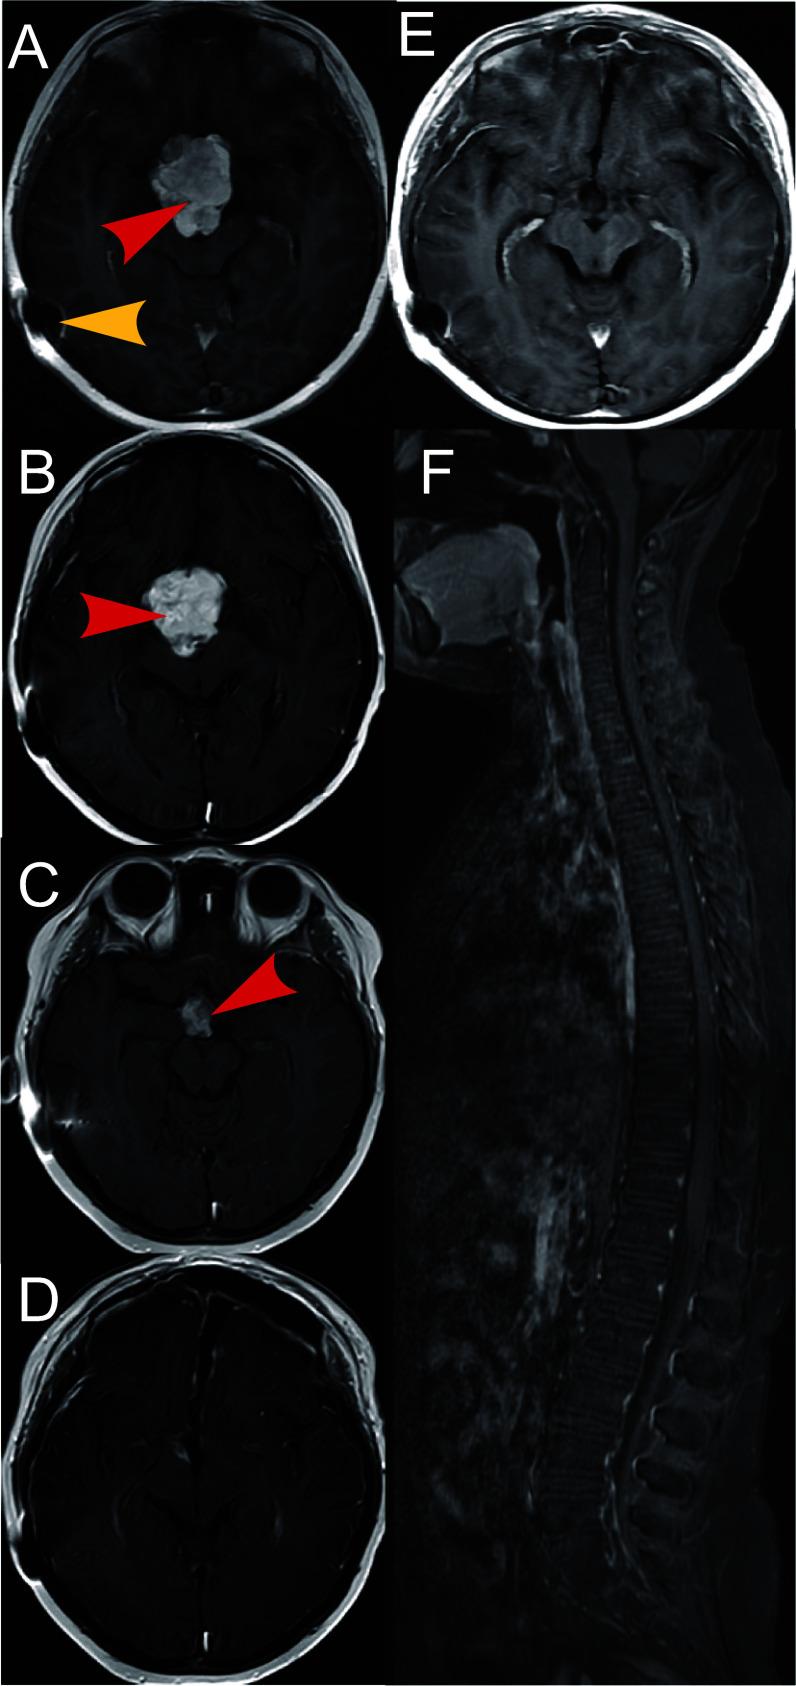

This disease is extremely rare, and the progression of metastatic germ cell tumors is often complex. All four patients underwent surgery, radiotherapy, and chemotherapy. In one case, the tumor spread to the anterior superior mediastinum via hematogenous metastasis; in two cases, it spread to the abdominal cavity through a ventriculoperitoneal shunt; and in one case, intraspinal spread occurred via cerebrospinal fluid. Over a follow-up period of 9 to 67 months, only one patient died from the disease. H&E and IHC staining confirmed pathological features. Analyzing dissemination introduced concepts like dynamics, components, mediums, ranges, portals, and patterns, creating a framework for understanding disease spread.